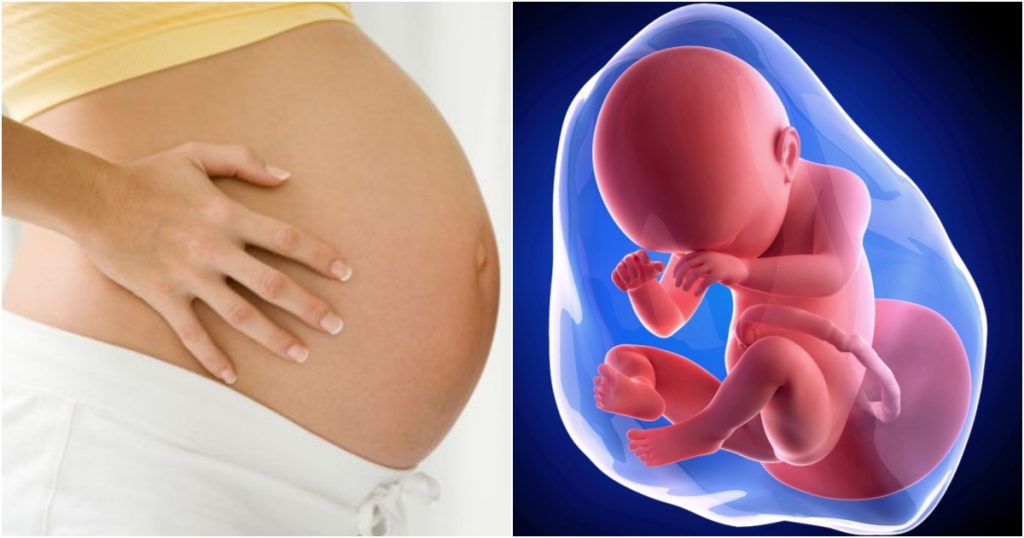

Thiếu ối 3 tháng đầu là gì?

Thiếu ối 3 tam cá nguyệt đầu là tình trạng lượng dịch trong buồng ối thấp hơn so với tuổi thai trong giai đoạn từ khi có thai đến hết tuần 13+6.

Nước ối trong tam cá nguyệt đầu hình thành từ đâu?

Trong 3 tháng đầu:

- Nước ối chưa phụ thuộc vào nước tiểu của thai

- Chủ yếu được tạo ra từ:

- Dịch thẩm thấu qua màng ối

- Dịch từ huyết tương của mẹ

- Hoạt động trao đổi sớm của bánh nhau